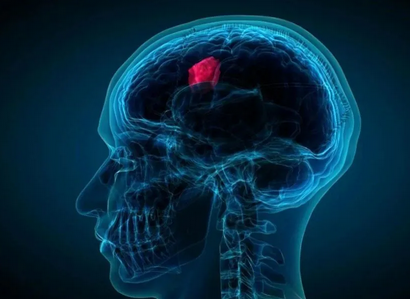

替莫唑胺是一种抗肿瘤药物,属于烷化剂类,主要通过抑制肿瘤细胞的DN*甲基化和错配修复来发挥抗肿瘤作用。该药物在体内可自发和很快地降解产生活性代谢物MTIC,临床常用于治疗胶质瘤、脑转移瘤等疾病。

胶质瘤四级吃替莫唑胺出现皮疹还能继续吃吗

脑瘤4级吃替莫唑胺出现皮疹一般不建议继续吃。替莫唑胺可用于脑瘤的治疗,如果在治疗期间出现了药物的不良反应,比如皮疹,一般建议及时停药,并在医生的指导下换药治疗。如果患者没有出现不良的反应,一般是可以继续吃的。在脑瘤的治疗期间,也可以配合激光治疗、电疗等方式来促进疾病的改善。